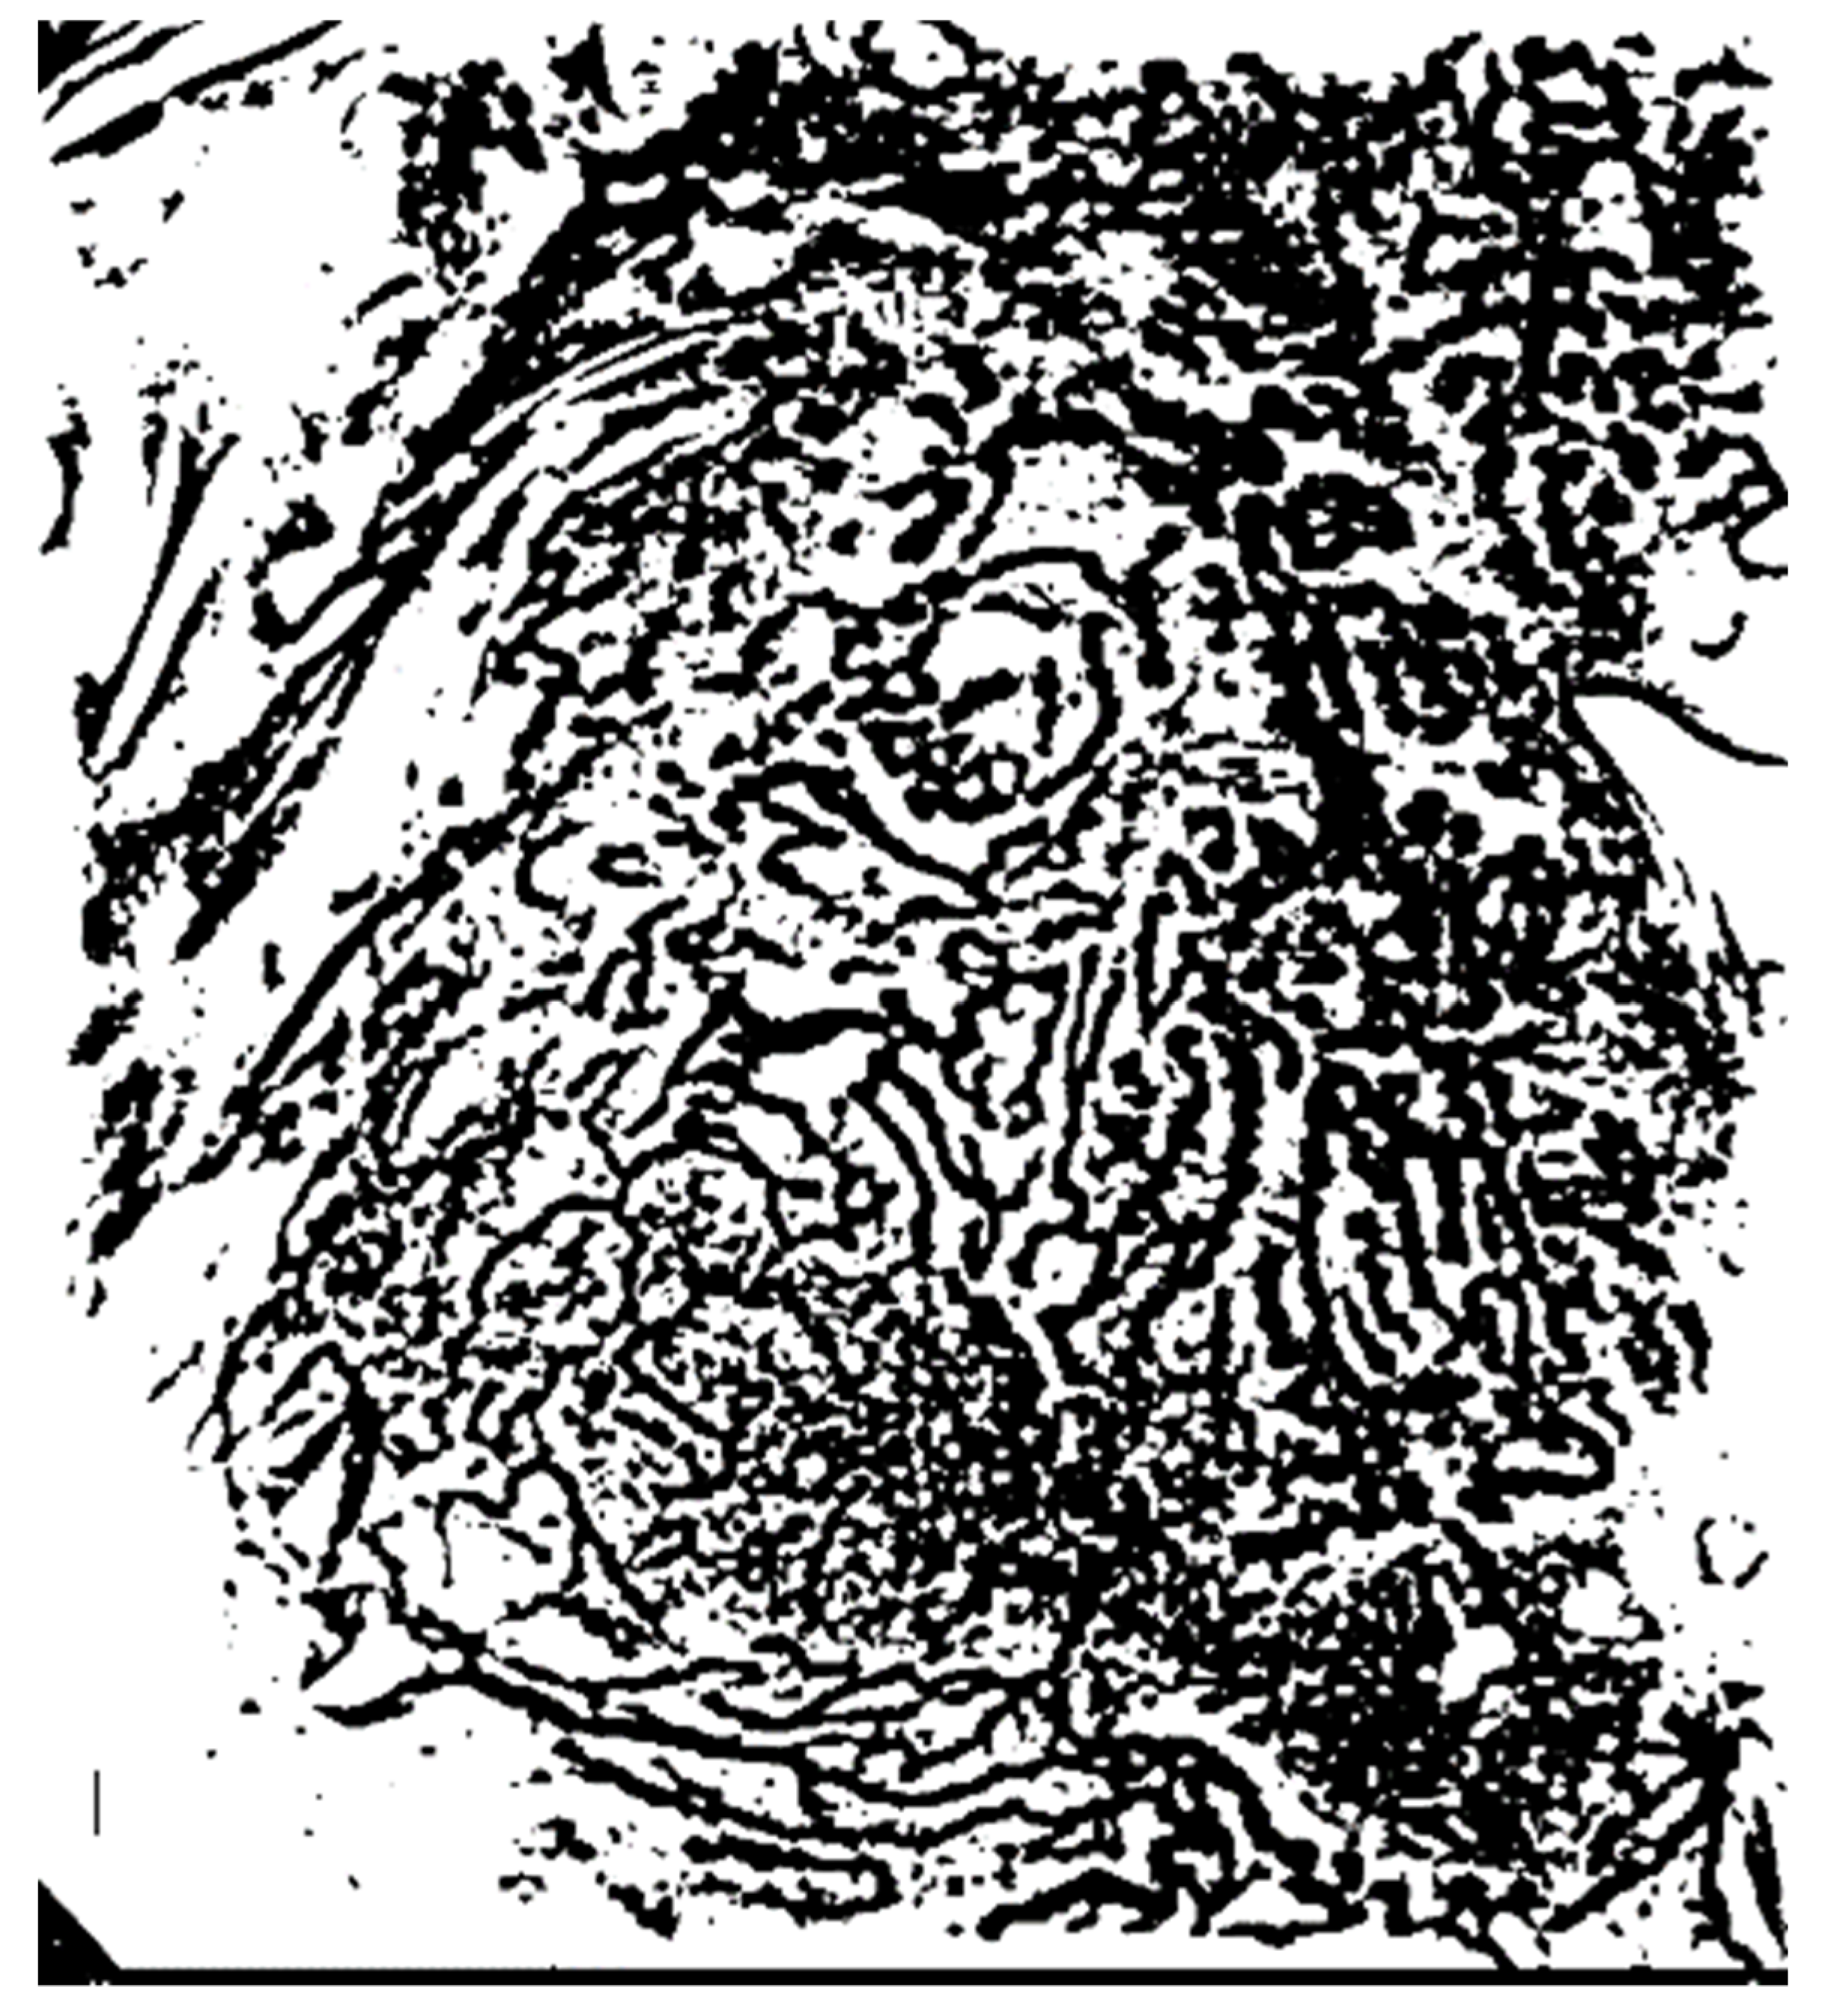

3.2.1. Extraction of the Microvessel Candidate Region Using Niblack’s Binarization

3.2.2. Noise Elimination in the Vascular Boundary Region Using a Fast Fourier High-Frequency Filter

3.2.3. Removal of the Background Area Using the ART2 Algorithm